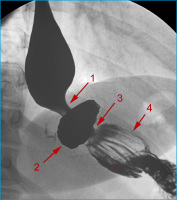

AGB

Abbildung 8: Bandleck nach AGB: Kontrastmittelinjektion in das Injektionsreservoir (1) mit wasserlöslichem, nichtionischem, isoosmolarem Kontrastmittel, über eine liegende Huber-Nadel (2). Der Katheter ist am Übergang zum Injektionsreservoir abgeknickt (3), wodurch es zu einem Kontrastmittelleck (4) kommt. Das Kontrastmittel der letzten Bandfüllung im Magenband (5) ließ sich am Beginn der Untersuchung nicht absaugen.

Keywords: GastroenterologieMagenbandRadiologie